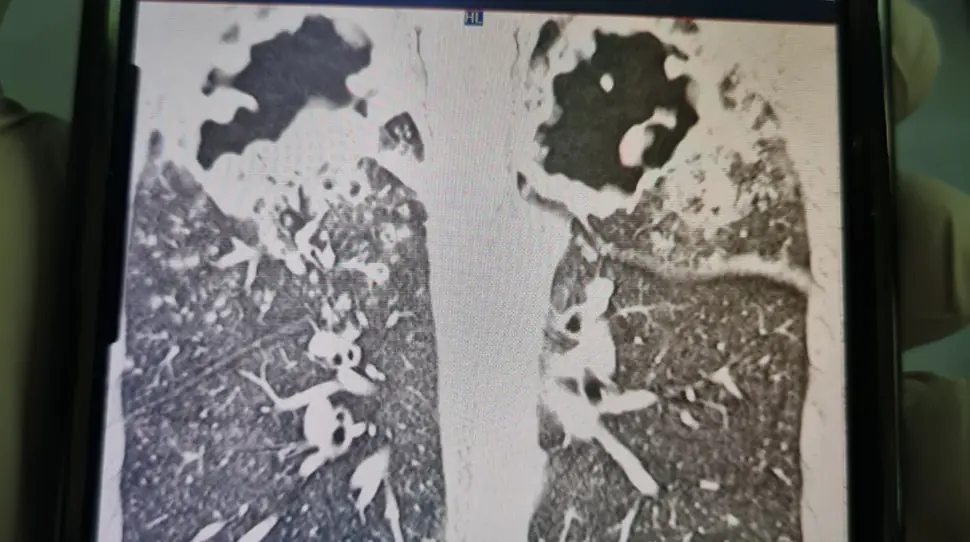

An X-Ray shows holes in Capper's lungs. Credit: GoFundMe

Before his diagnosis, an X-ray revealed a hole in Capper's lungs, and within just six weeks, the infection had consumed a third of his lung tissue.